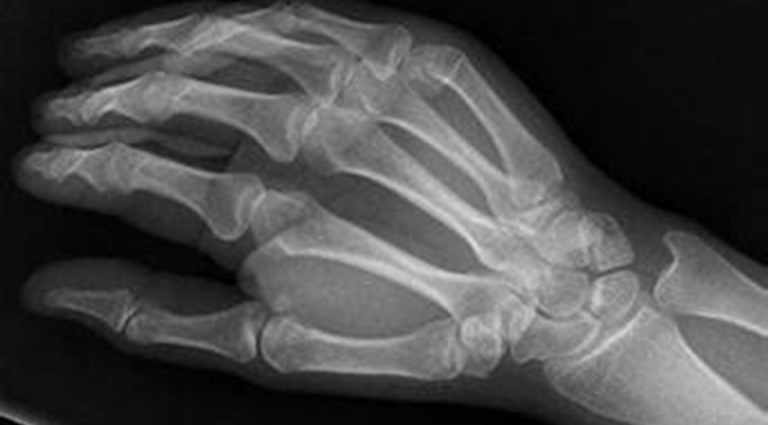

Here are the x ray results and the CT results.

12/6/2023 On x ray “….. appearance of proximal fourth metacarpal, concerning for nondisplaced fracture. Distal radial mild cortical irregularity, concerning for nondisplaced fracture of the distal radius.”

12/14/2023 On CT “…..no fractures identified on this exam. There is no distal radius fracture identified.”

Prayer was 12/12/2023

Comment: Left to heal by themselves, bones do not heal in 8 days but more like 6 to 8 weeks. This was the Lord’s doing and nothing else can explain it. He deserves all the praise and the glory.